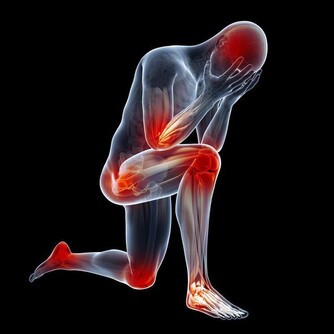

3.脾胃問題

放屁很多那說明你身體肯定出了問題,如果很臭屁,放屁是由胃冷引起的;

不太臭,酸,大便是腹瀉,肚子冷,有可能是腸炎。